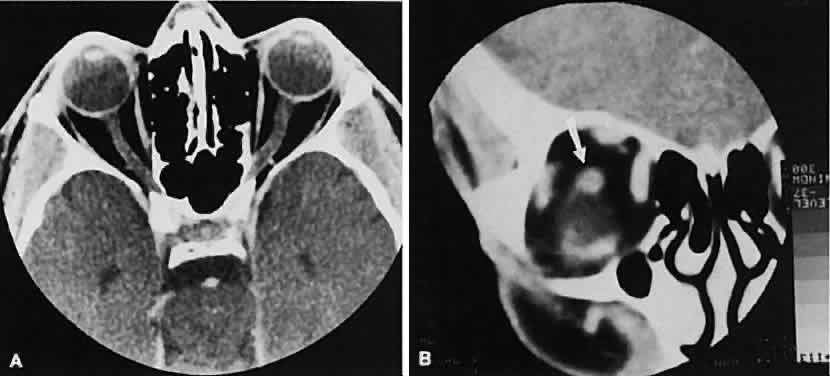

An appreciation for the various pathologic processes that affect the orbit is facilitated by an understanding of the normal orbital anatomy (Fig. 1). The orbit is a pyramid-shaped bony structure bounded inferiorly by the maxillary sinus, medially by the ethmoidal sinus, and superiorly by the frontal sinus. The sphenoidal sinus is situated posteriorly along the medial orbital wall and has a common wall with the optic canal. The lacrimal gland lies within its fossa located in the superior temporal aspect of the orbit and can be seen on both axial and coronal views.

The extraocular muscles (EOMs), with the exception of the inferior oblique, originate from the anulus of Zinn in the orbital apex. The inferior oblique takes its origin from the frontal process of the maxilla and is seen occasionally on CT imaging. The superior oblique, after originating from the anulus, courses along the superior nasal orbital wall just above the medial rectus muscle before passing through the trochlea. The rectus muscles conveniently form a muscle cone, which is sometimes helpful in terms of differential diagnosis. Before thinner axial slices and multiplanar imaging were available, an enlarged inferior rectus muscle often was imaged as an apical mass, especially if dysthy-roid optic neuropathy was present. The importance of imaging from two different planes cannot be overemphasized in this situation.

The superior ophthalmic vein (SOV) is an important vascular structure to recognize. It begins in the superior nasal quadrant near the trochlea before coursing posteriorly and laterally beneath the superior rectus muscle, exiting the orbit through the superior orbital fissure. Drainage is into the cavernous sinus. Asymmetric enlargement, especially in the presence of an ipsilateral cavernous sinus enlargement, suggests a vascular anomaly, which may require selective carotid angiography for further definition. Enlargement of one or multiple EOMs in this setting is likely. The SOV also may be enlarged as a result of any process impeding drainage from the orbital apex, such as dysthyroid orbitopathy or metastatic disease.

The optic nerve occupies the central intraconal space. By necessity, the nerve has a certain amount of slack, which is necessary to permit movement of the globe. In the axial plane, the optic nerve has an undulating course and thus may appear thicker or thinner as a result of partial volume averaging as it passes in and out of the axial plane. It is imperative to recognize this normal pattern for proper interpretation of axial images.

The optic nerve itself is invested by the same meningeal layers that cover the brain, and the intracranial space may extend along the course of the optic nerve to the back of the globe. Enlargement of this space may be recognized as pseudomeningoceles of the optic nerve sheath. It is sometimes possible to tell whether the nerve, the sheath, or both are enlarged by CT scanning, although MRI affords the better view.